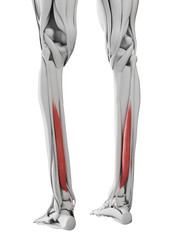

Podobny obraz Medical Elbow Anterior View X-Ray Radiograph Illustrating...